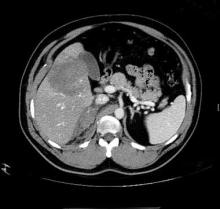

Case. A 48-year-old construction worker presented to the ED after he was struck in the right lower chest by a spinning metal drill at a pressure of 1000 psi (torque). Although a focused abdominal sonography for trauma scan was negative, contrast-enhanced computed tomography revealed a large complex liver laceration (red oval, Figure) in the right lobe and a right adrenal hematoma (yellow arrow, Figure).

As part of initial assessment and resuscitation in the ED, severely injured trauma patients frequently undergo a bedside focused abdominal sonography for trauma (FAST) scan to assess for intraperitoneal hemorrhage from an underlying major abdominal visceral injury, as well as the presence of pleural and/or pericardial effusion. However, the use and role of a FAST scan in hemodynamically stable patients has recently been questioned since, based on its relatively low sensitivity for visceral injury, many of these cases eventually require computed tomography (CT) (See Case). In addition, patients in this subset with a positive FAST scan frequently have subsequent CT to further assist clinicians in understanding the nature of injury and to guide management recommendations (eg, operative versus nonoperative options).1